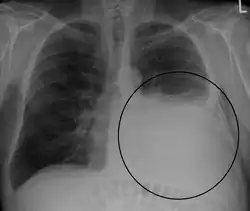

A pleural effusion appears as an area of whiteness on a standard posteroanterior chest X-ray.[15] Normally, the space between the visceral pleura and the parietal pleura cannot be seen. A pleural effusion infiltrates the space between these layers. Because the pleural effusion has a density similar to water, it can be seen on radiographs. Since the effusion has greater density than the rest of the lung, it gravitates towards the lower portions of the pleural cavity. The pleural effusion behaves according to basic fluid dynamics, conforming to the shape of pleural space, which is determined by the lung and chest wall. If the pleural space contains both air and fluid, then an air-fluid level that is horizontal will be present, instead of conforming to the lung space.[16] Chest radiographs in the lateral decubitus position (with the patient lying on the side of the pleural effusion) are more sensitive and can detect as little as 50 mL of fluid. Between 250 and 600mL of fluid must be present before upright chest X-rays can detect a pleural effusion (e.g., blunted costophrenic angles).[17]

Pleural effusion as seen behind the heart.[20]

Massive pleural effusion, later proven to be hemothorax in a South Indian male.